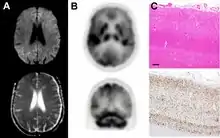

Brain FDG PET-CT tends to be markedly abnormal, and is increasingly used in the investigation of dementias.

- Patients with CJD will normally have hypometabolism on FDG PET.[50]

Histopathology

Testing of tissue remains the most definitive way of confirming the diagnosis of CJD, although it must be recognized that even biopsy is not always conclusive.[51]

The classic histologic appearance is spongiform change in the gray matter: the presence of many round vacuoles from one to 50 micrometers in the neuropil, in all six cortical layers in the cerebral cortex or with diffuse involvement of the cerebellar molecular layer.[54] These vacuoles appear glassy or eosinophilic and may coalesce. Neuronal loss and gliosis are also seen.[55] Plaques of amyloid-like material can be seen in the neocortex in some cases of CJD.[56]